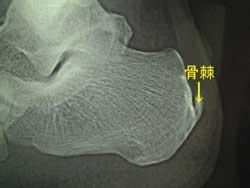

导读: 骨质增生即人们常说的骨刺,腰椎骨质增生则是骨骼衰老,退行性改变的表现。骨刺只是长在骨的外部,并非长在骨内,本身无神经,因此,一般不会感觉疼痛。但若骨刺压迫了脊髓或脊神经,病人会感到肢体麻木、眩晕、头痛

•  微创治疗骨刺怎么样

导读: 微创治疗骨刺怎么样?骨刺是一种很严重的骨科疾病,病发后患者会感觉全身酸痛,疼痛难忍,骨刺的产生让中老年人遭受了许多的困扰。在确诊骨刺后,一定要积极的进行治疗。而治疗骨刺的方法有很多,如保守治疗、手术治